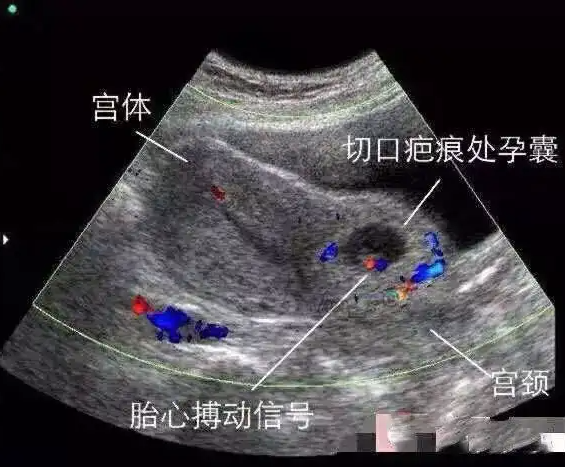

【中国医师节·科室风采】用专业精心呵护女性健康——妇科

广西科技大学第一附属医院妇科始于建院,经过几代妇科人的沉淀,目前已发展成为一个集临床、科研、本科教学、住院医师规范化培训为一体的科室,为医院终点站换壳。高级职称的“双师型”(医师、高校教师)人才9人,拥...